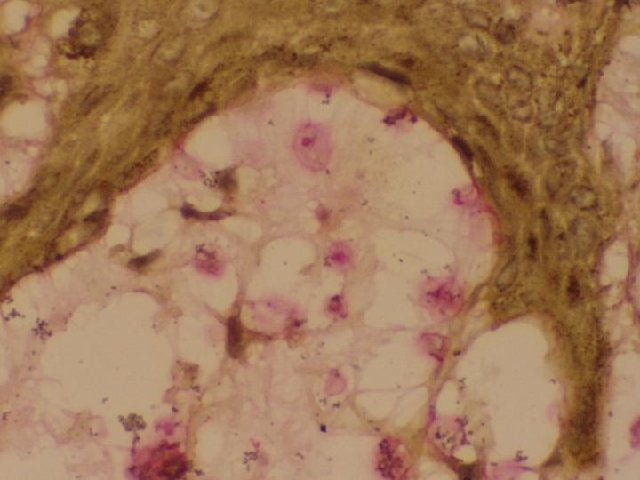

His skin biopsy revealed numerous organisms of various sizes surrounded by capsules, which stained positive with mucicarmine in the superficial and deep dermis, with very little inflammatory response. (Fig 3,4)

Fig. 4. Mucicarmine stain of 3mm punch biopsy at 40X showing the characteristic red staining capsule in the superficial dermis